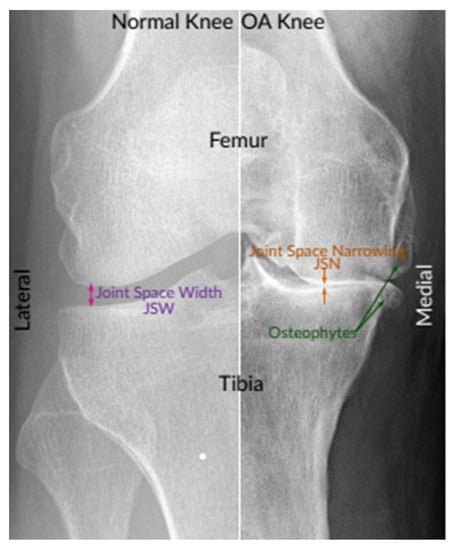

Osteoarthritis

An instance of X-ray images of the normal knee and severe OA knee. On the left is a normal knee, and on the right is an OA knee. This image shows joint compartments, as well as joint space narrowing (JSN) and osteophytes

Osteoarthritis (OA) is the most common form of arthritis, often referred to as “wear and tear” arthritis. It can affect any joint in the body, including the knee.